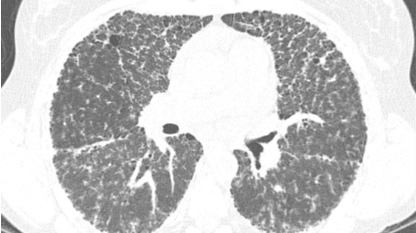

Sarcoidosis phổi là một tình trạng bệnh lý trong đó các u hạt (granulomas), là những cụm tế bào viêm nhỏ, hình thành trong phổi. Đây là biểu hiện phổ biến nhất của bệnh sarcoidosis, một bệnh viêm hệ thống có thể ảnh hưởng đến bất kỳ cơ quan nào trong cơ thể, nhưng thường bắt đầu ở phổi và hạch bạch huyết.